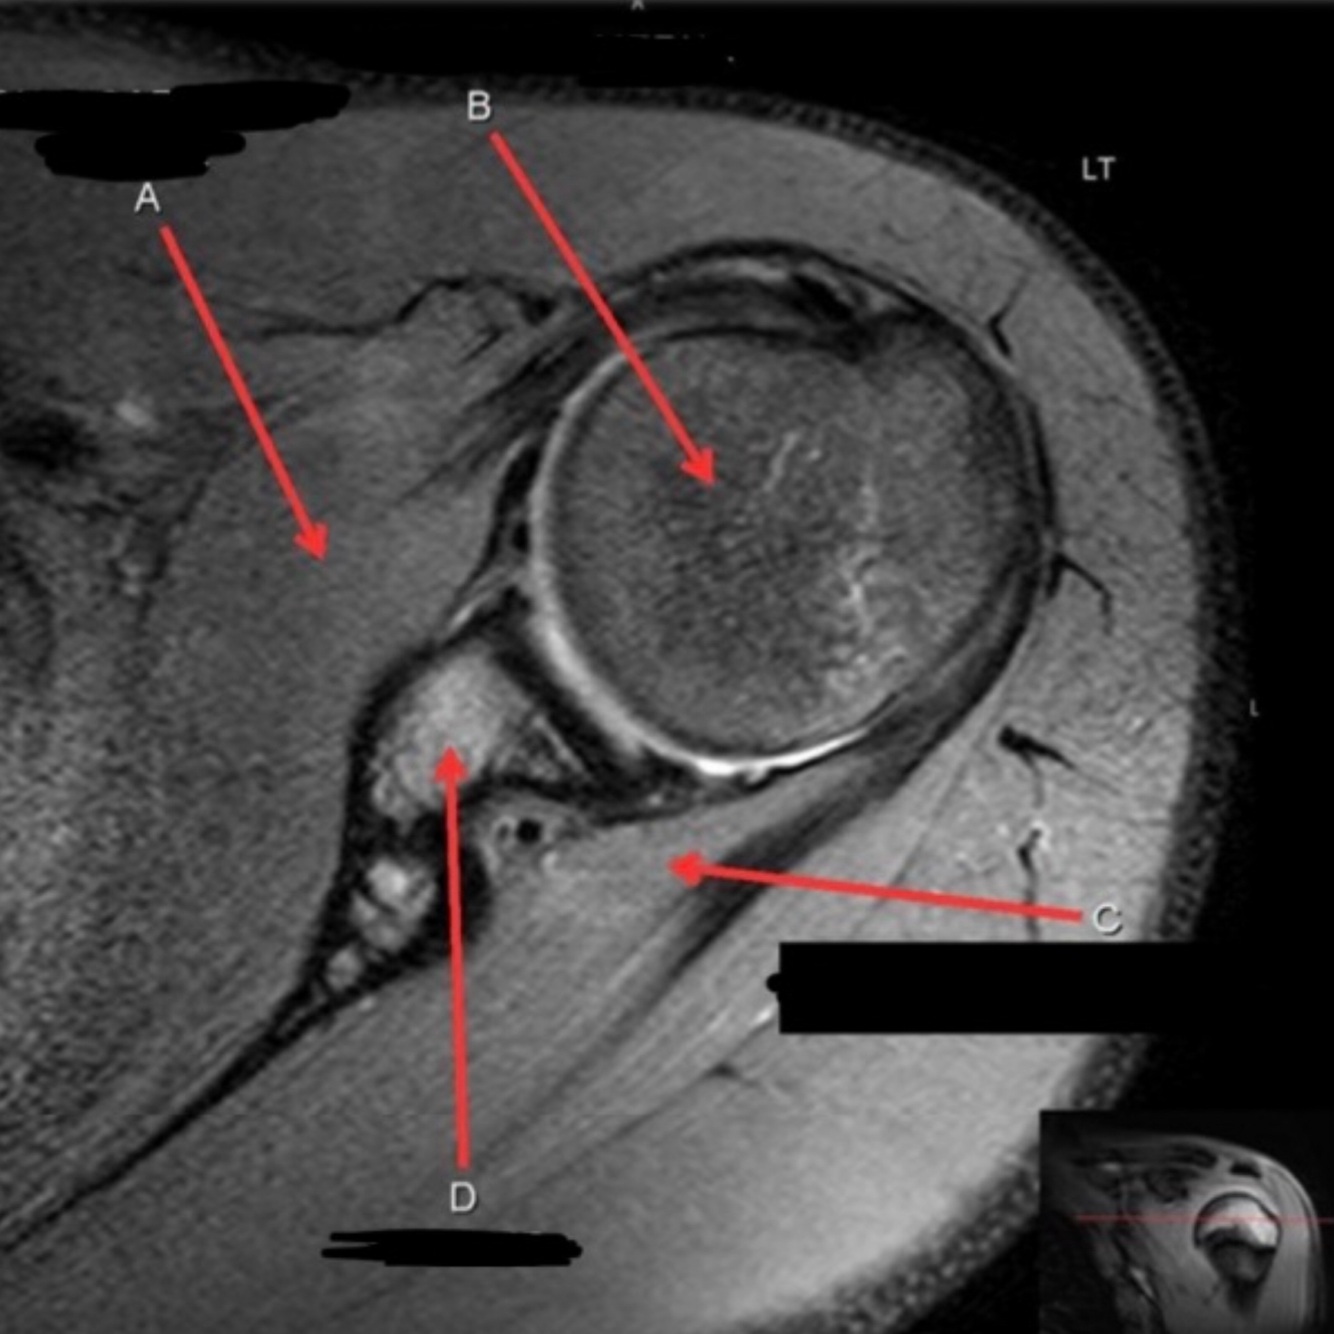

What is letter A?

A

SUBSCAPULARIS MUSCLE

How well did you know this?

Q

What is letter B?

HEAD OF HUMERUS

9

What is letter C?

INFRASPINATUS MUSCLE

10

What is letter D?

GLENOID

1

Not at all

2

3

4

5

Perfectly

11

ANTERIOR LABRUM

12

BICEPS TENDON (LONG HEAD)

13

14

POSTERIOR LABRUM